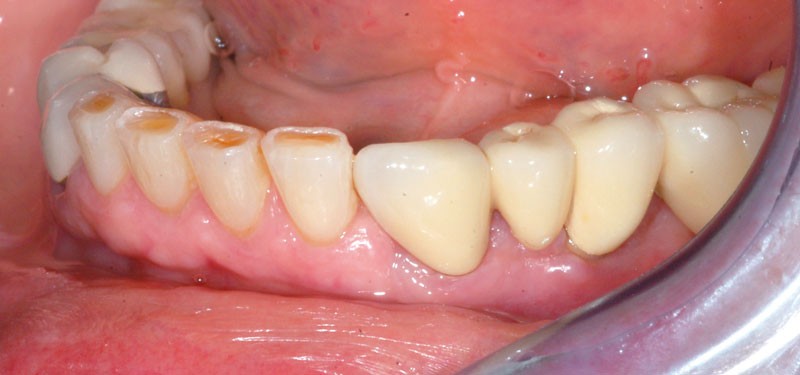

Après dépose du bridge mandibulaire et reprise du traitement endodontique, un bridge transitoire est réalisé à partir du wax-up. Une empreinte de celui-ci est faite avec Imprint™ 4 Preliminary Penta™ (3M ESPE).

L’automoulage est garni avec une résine composite (Protemp™ 4, 3M ESPE), avant ajustage et finition (roues spirales Sof-Lex™, 3M ESPE), pose du bridge transitoire.